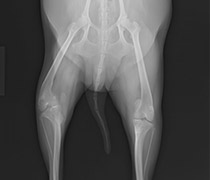

また、動物医療の高度化に伴い、外科手術の必要性は高くなっています。

当院では、腫瘍外科、整形外科、神経外科、軟部外科、眼科など様々な外科手術に対応しています。